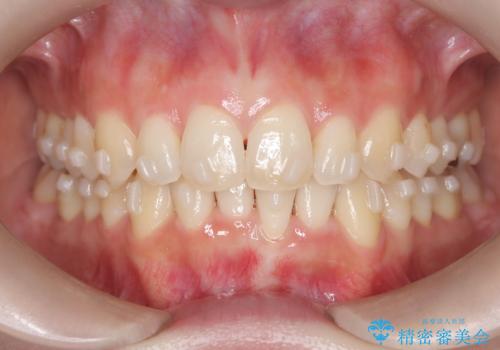

インビザラインで整えた前歯の歯並び

- 患者様は、上下前歯の歯列不正(ガタガタ)を主訴としてご来院されました。治療計画として、透明なマウスピース型矯正装置「インビザライン」を使用し、約2年の期間を見込んで前歯部の歯列を整える方針を立てました。特に下顎前歯に歯肉退縮のリスクがあるため、治療中にIPR(インタープロキシマルリダクション)を行い、歯間を適切に削ることで、過度な圧力を避け、歯肉退縮を防ぎながら配列を進めました。治療は慎重に進め、最終的にきれいで整った前歯の歯並びを目指しました。